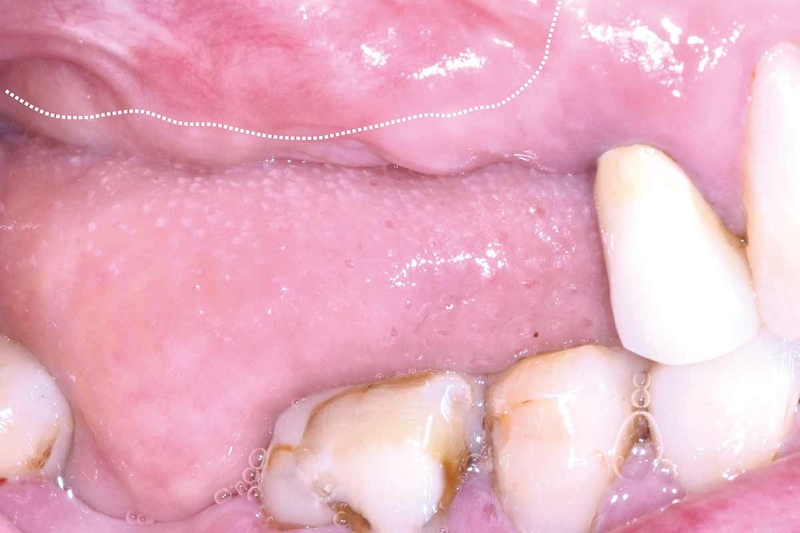

Bệnh u nhú tiền đình là sự xuất hiện của những khối u nhỏ, tròn, có màu da trên âm hộ của phụ nữ, đặc biệt là ở phần bên ngoài của âm đạo. Những khối u này có thể tụ lại thành hàng hoặc mảng đối xứng trên môi âm hộ. Ngoài ra, chúng cũng có thể xuất hiện ở tiền đình, vùng lỗ mở của âm đạo được bao quanh bởi môi âm hộ.

Tính chất của các u nhú này có thể là những nốt mụn tròn nhẵn hoặc hình đầu ngón tay, với đường kính khoảng 1 - 2 mm. Chúng thường phát triển chậm. Mặc dù không nguy hiểm và không được coi là bệnh lây nhiễm qua đường tình dục, các chuyên gia khẳng định rằng u nhú tiền đình không gây hại.

Các vết sưng trên tiền đình có dạng những nốt nhỏ, trơn, không đau và có màu da. Chúng có thể có hình tròn giống như mụn cơm hoặc dài hơn, thường có đường kính từ 1 - 2 mm. Những người bị u nhú tiền đình thường không có bất kỳ triệu chứng nào khác.

Tuy nhiên, có một số điểm khác biệt giữa hai bệnh này. U nhú tiền đình có các nốt mọc đối xứng hoặc thành dải, có màu sắc tương đồng với màu da niêm mạc. Trong khi đó, sùi mào gà có các nốt mọc một cách không đều, xen kẽ lẫn nhau.

Ngoài ra, u nhú tiền đình chỉ có một chân, trong khi sùi mào gà có thể phát triển thành nhiều nốt sùi từ một nguồn gốc. Với trường hợp chưa có quan hệ tình dục hoặc không sử dụng đồ vật chung với người khác mà có các nốt sần, khả năng cao đó là u nhú tiền đình chứ không phải sùi mào gà.